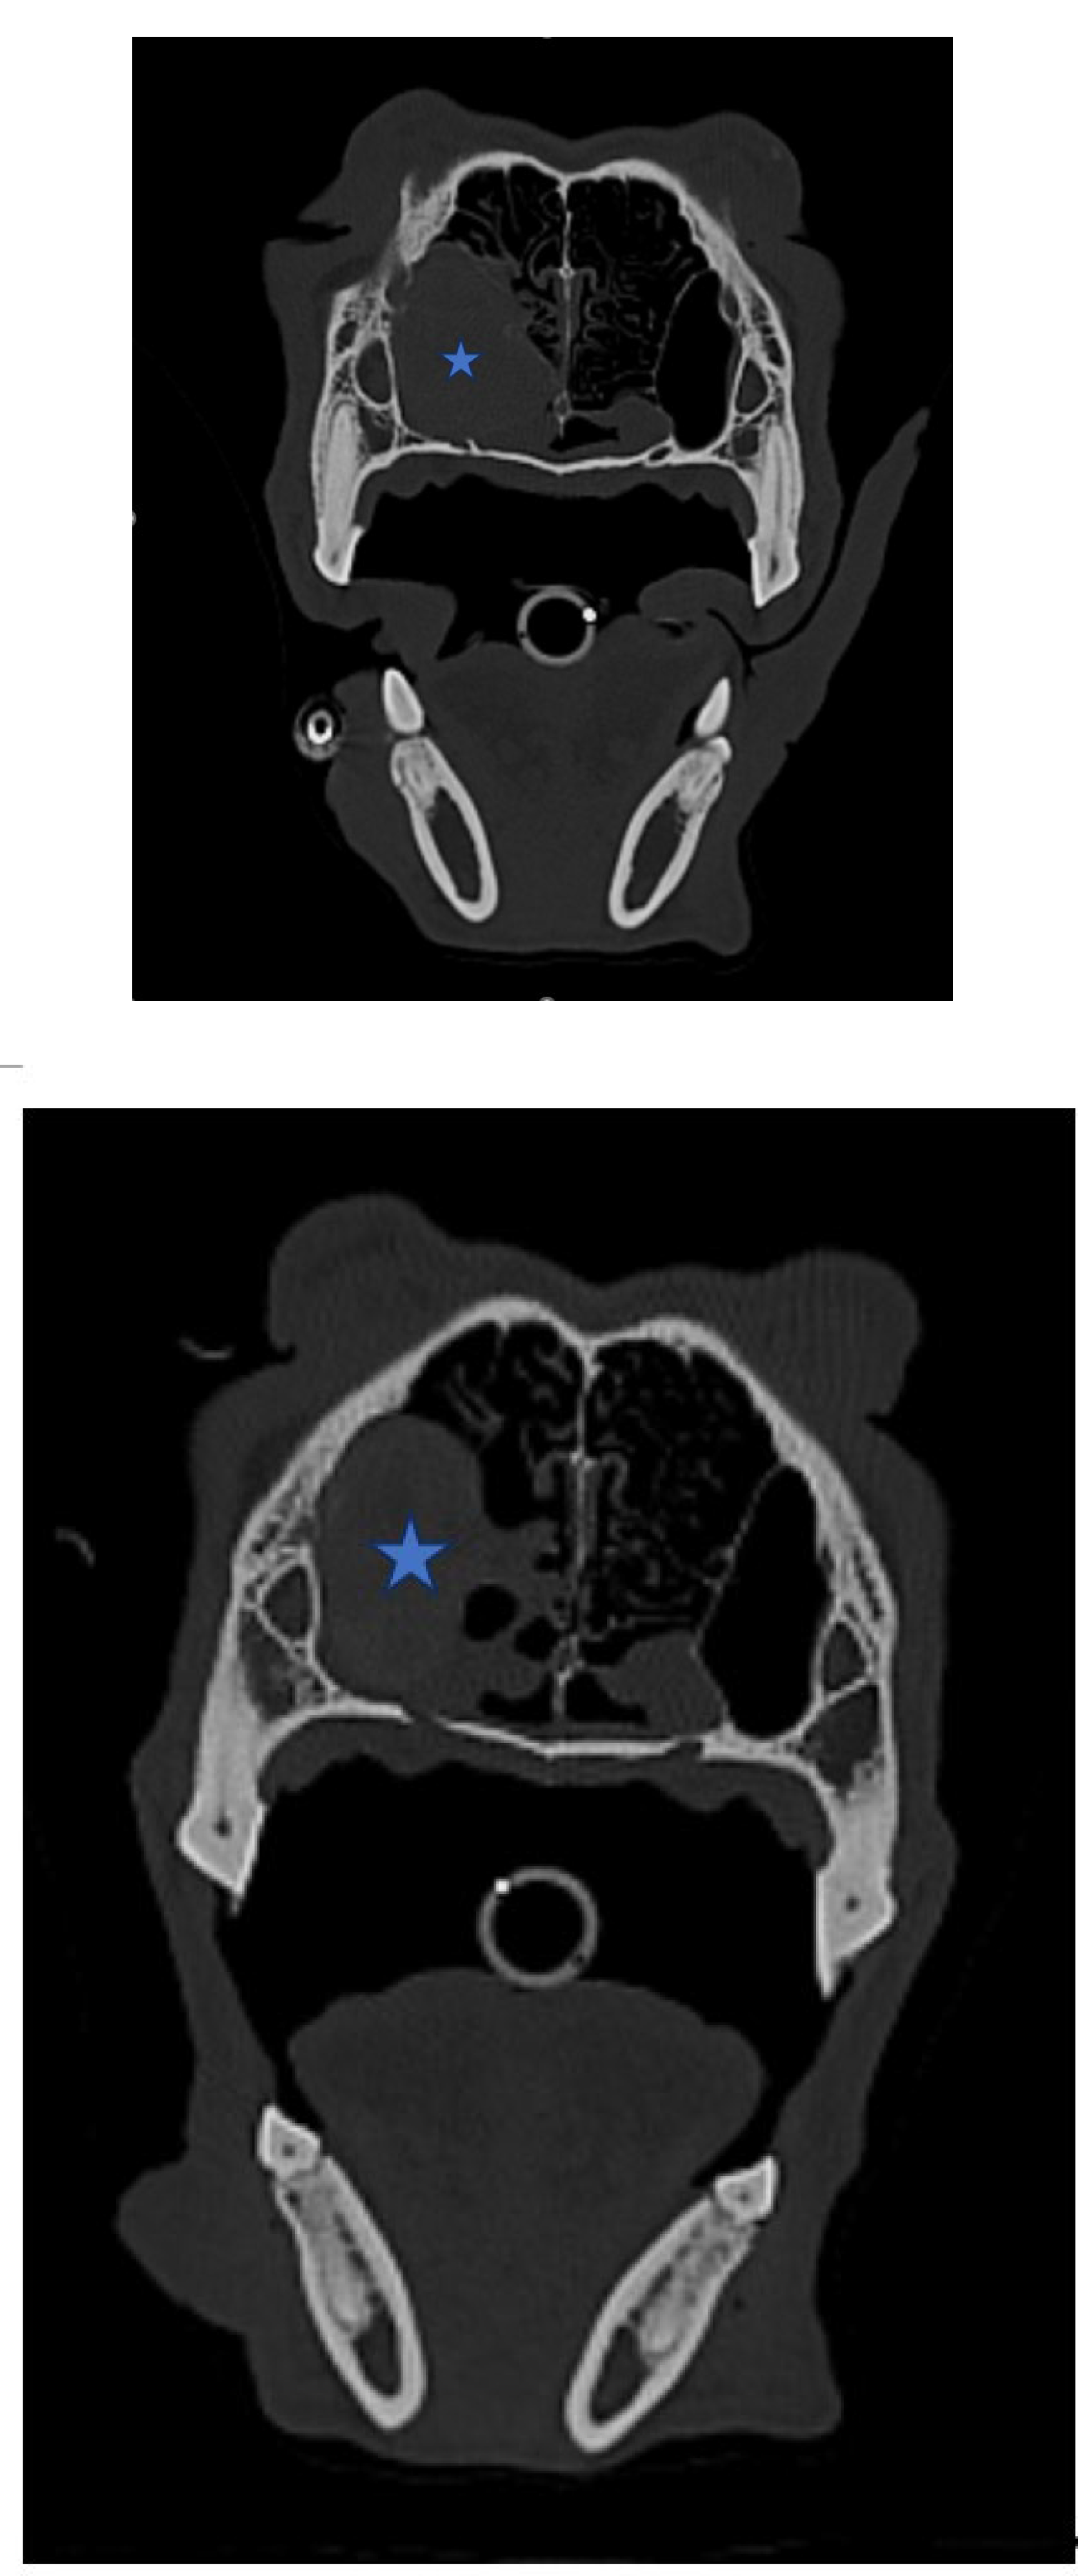

Figure 2. (A,B,C). Axial View of CT Scan of Skull

The size of the tumor decreased significantly after radiation/chemotherapy compared with before radiation/chemotherapy, after radiation, and before chemotherapy (Asteroid).